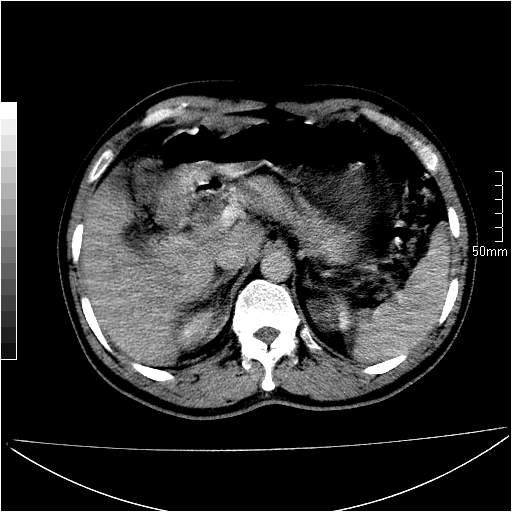

男性,54岁,皮肤黄染,搔痒一周余.b超示肝左叶回声异常.初步诊断1胆总管下段结石2胆囊结石伴慢性胆囊炎请各位战友帮忙看一下肝脏多发低密度如何解释恰当.增强效果不是很好.请大家见谅.

胆总管及肝内胆管扩张,考虑是结石!但,肝内的低密度区增强不明,可能是肝ca,因为肝ca在增强时呈快进快出.另年胆总管扩张原因,可以考虑一下是不是,胆管ca.再次要考虑肝内的低密度是否为海绵状血管瘤所致!

首先,胆总管下端结石梗阻伴肝内胆管扩张可确定。

另外,肝八段低密度占位,呈多灶性,考虑肝脓肿或肝癌可能,(图像质量欠佳)建议进一步检查。

既然做了增强,为什么光提供延时期片子,肝动静脉期肝右叶前下段病灶增强如何?另外胆囊壁增厚,欠规整,内密度不均,与肝右叶病灶分界不清,增强表现怎样?肝内胆管轻度扩张,胆总管扩张,但未见明显结石影,也应提供增强早期图像才好鉴别扩张原因。片子较清,但不够完整,暂考虑1.胆囊癌肝局部浸润,或肝癌胆囊侵犯,2.胆总管下端或胰头钩突部占位。总之本人看不明白,请高手画图指示,先谢了!

由于胆囊窝内结构显示不清,肝脏病灶又邻近胆囊窝首先考虑胆囊癌肝受侵犯。而后因肝脏病灶强化有渐进改变,且相邻胆管扩张,故考虑肝胆管细胞癌待排。

左肝胆管细胞癌。

胆总管下端结石。